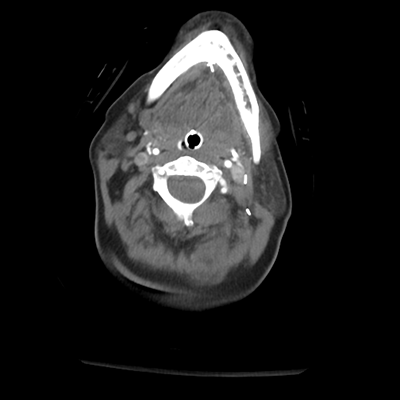

CTA head/neck

CTA head/neck 1/36 1/36

CTA head/neck 2/36 2/36

CTA head/neck 3/36 3/36

CTA head/neck 4/36 4/36

CTA head/neck 5/36 5/36

CTA head/neck 6/36 6/36

With the CTA of her head/neck, we can sort of see some atherosclerosis (though the images aren't windowed well for this). Importantly, though, we can see a rounded abnormality around the tip of the basilar/left PCA. This is an aneurysm! This helps put things together. This patient had an aneurysmal rupture leading to SAH and hydrocephalus, causing her loss of consciousness. While her leg extensor movements could be seizures, they're probably actually posturing movements, secondary to intracranial hypertension in the setting of her hydrocephalus.